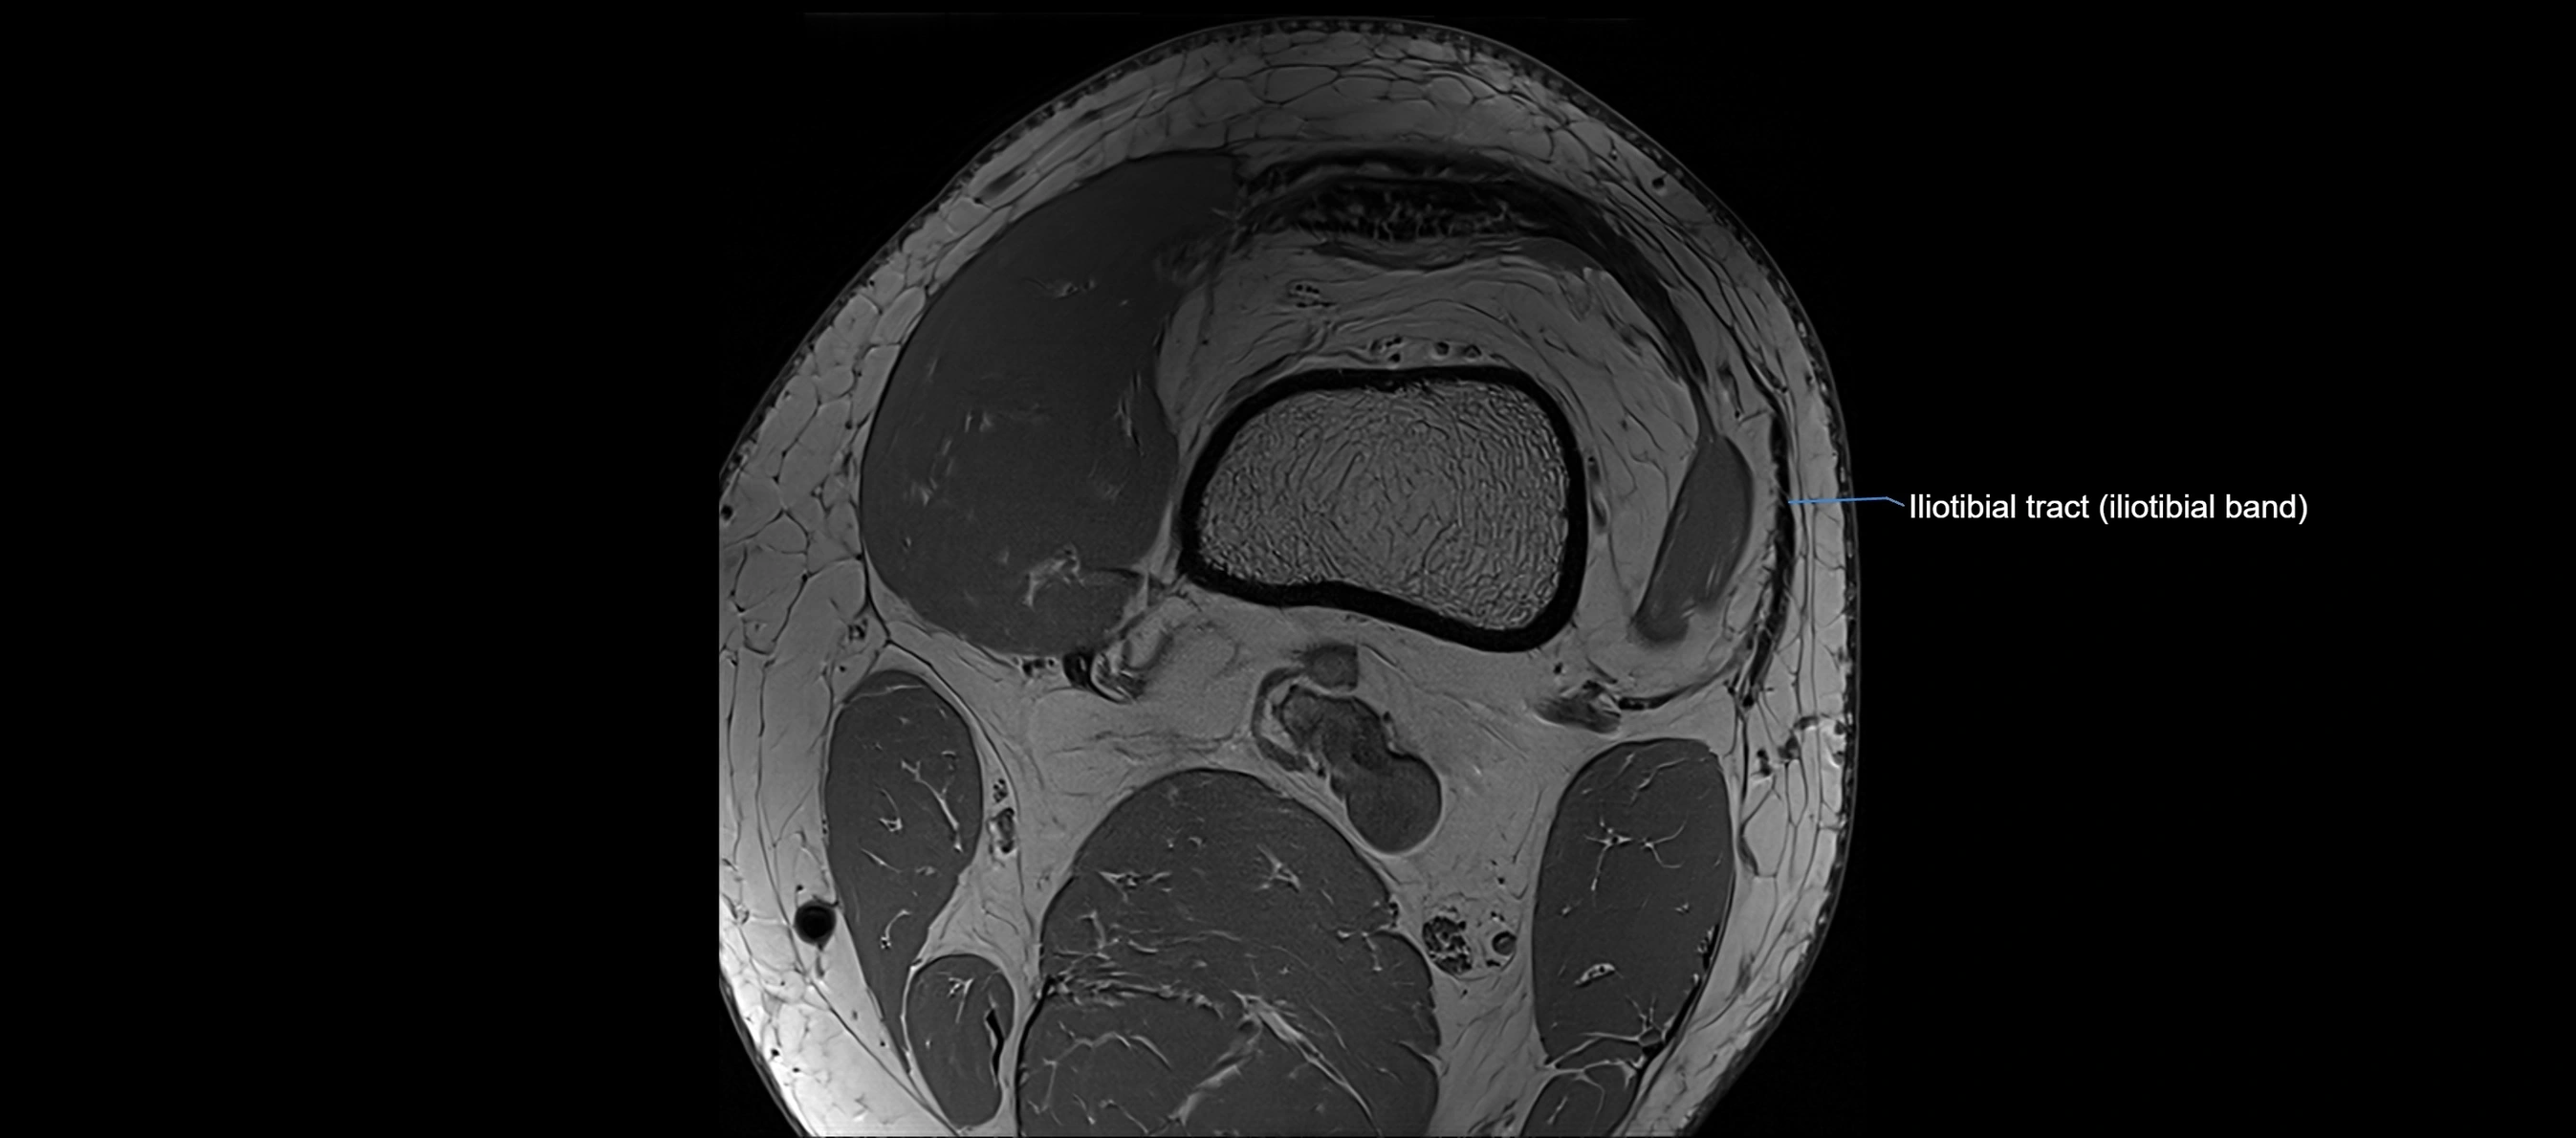

MRI images

image